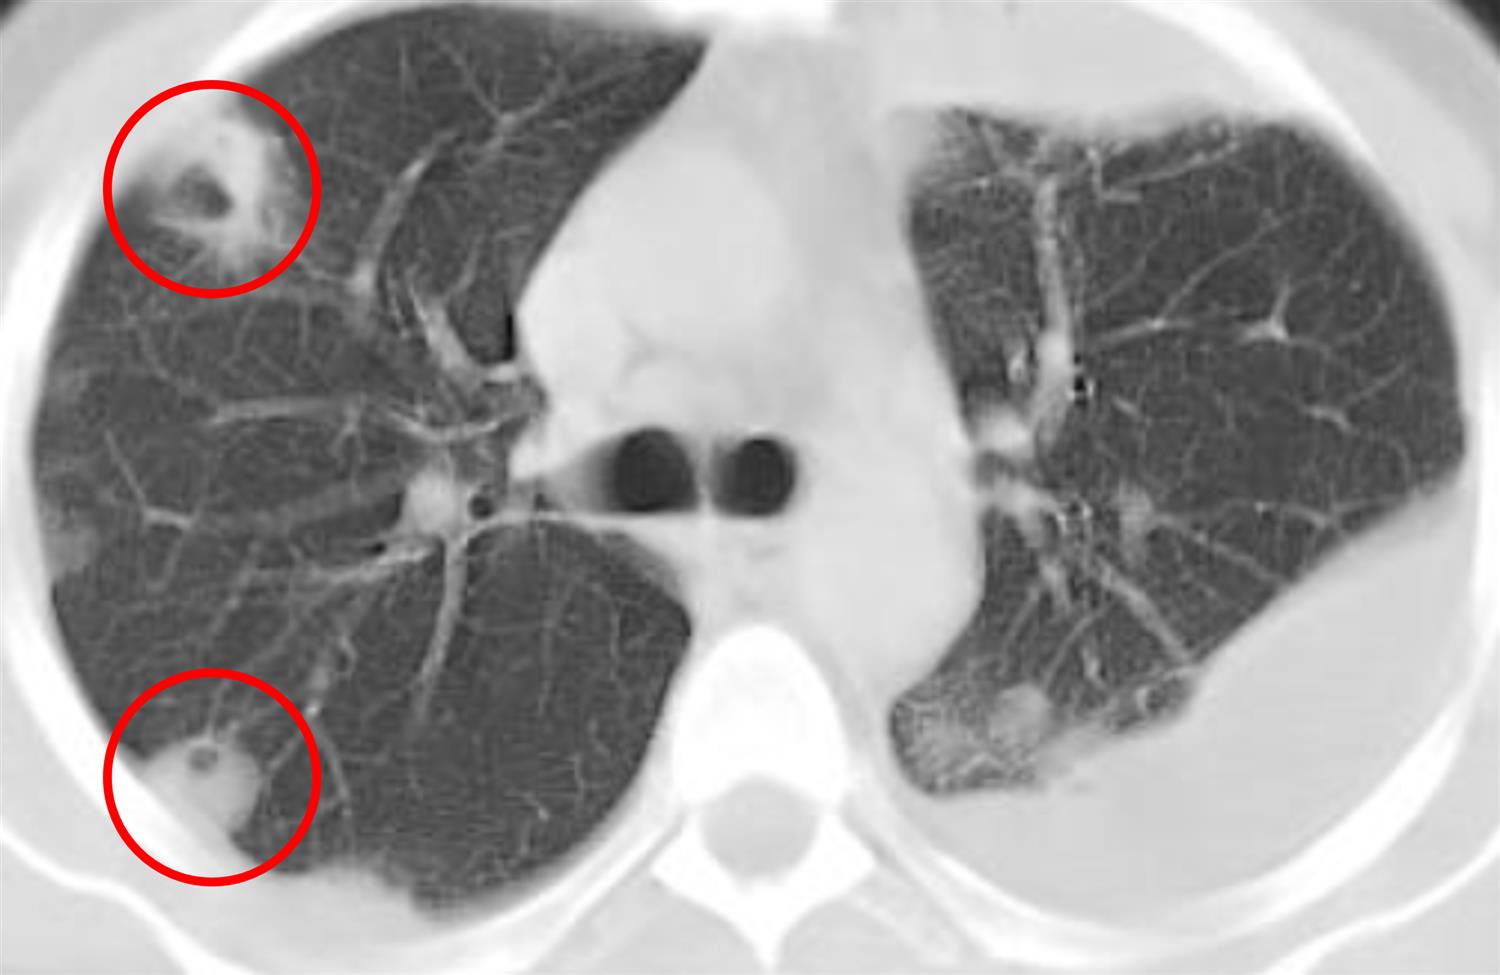

A 26-year-old man presents to the emergency department with a 3-day history of fever and malaise. He says that the fever started after he came back from a bachelor party and admits to using intravenous drugs while partying during that trip. He has no significant medical history and does not take any medications. He is a graduate student and has between 10 and 15 drinks per week. He has no smoking history and intermittently uses intravenous drugs. His temperature is 102.2°F (39°C), blood pressure is 106/67 mmHg, pulse is 103/min, and respirations are 16/min. A physical exam reveals injection marks on his arms bilaterally. Cardiac auscultation reveals a high-pitched holosystolic murmur best heard at the left lower sternal border. A CT scan is obtained, and the results are shown in Figure A. After obtaining blood cultures, which of the following is the most appropriate initial treatment for this patient?

This patient, who presents with a history of intravenous drug use, persistent fever, malaise, a murmur consistent with tricuspid regurgitation, and a CT scan with septic emboli, most likely has acute bacterial endocarditis. The empiric treatment for this disease in a patient with native valves is vancomycin and cefepime.

Figure/Illustration A is a CT scan of the chest demonstrating septic emboli (red circles). These findings are consistent with endocarditis caused by Staph aureus.